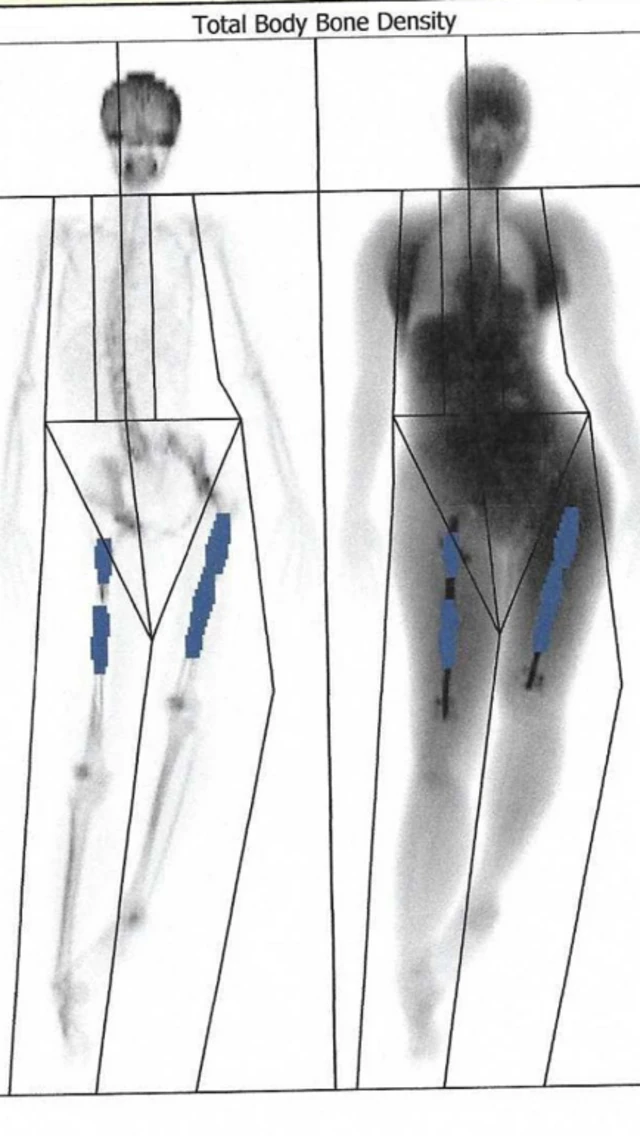

ਸਤੰਬਰ ਤੱਕ ਉਨ੍ਹਾਂ ਦੀ ਸੱਜੀ ਲੱਤ ਸੱਤ ਸੈਂਟੀਮੀਟਰ ਵਧ ਗਈ ਸੀ। ਪਰ ਚੀਜ਼ਾਂ ਆਮ ਵਾਂਗ ਨਹੀਂ ਚੱਲ ਰਹੀਆਂ ਸਨ। ਉਨ੍ਹਾਂ ਦੀਆਂ ਦੋਵੇਂ ਲੱਤਾਂ ਵੱਡੀਆਂ-ਛੋਟੀਆਂ ਸਨ, ਜਿਸ ਕਾਰਨ ਉਨ੍ਹਾਂ ਦੀ ਰੀੜ੍ਹ ਦੀ ਹੱਡੀ ਟੇਢੀ ਹੋ ਗਈ ਅਤੇ ਉਨ੍ਹਾਂ ਨੂੰ ਲਗਾਤਾਰ ਦਰਦ ਦੀ ਸ਼ਿਕਾਇਤ ਹੋਣ ਲੱਗੀ।

ਛੇ ਹਫ਼ਤਿਆਂ ਬਾਅਦ ਹੋਏ ਸਕੈਨ ਤੋਂ ਪਤਾ ਲੱਗਾ ਕਿ ਉਨ੍ਹਾਂ ਦੀ ਸੱਜੀ ਲੱਤ ਦੀਆਂ ਹੱਡੀਆਂ ਨੇ ਵਧਣਾ ਬੰਦ ਕਰ ਦਿੱਤਾ ਸੀ। ਇਸ ਲੱਤ 'ਚ ਫੀਮਰ ਦੇ ਦੋ ਟੁਕੜੇ ਰਾਡ ਨਾਲ ਜੁੜੇ ਹੋਏ ਸਨ।